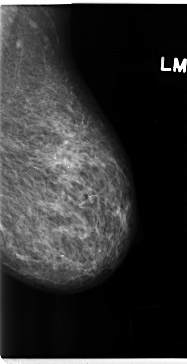

C_0184_1.LEFT_MLO

LEFT_MLO LINES 4720 PIXELS_PER_LINE 2424 BITS_PER_PIXEL 12 RESOLUTION 50 NON_OVERLAY